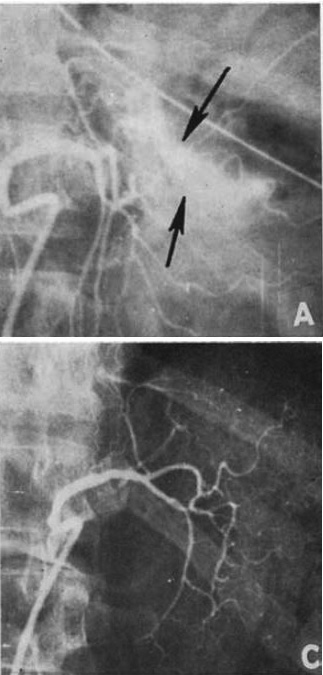

図2.骨盤内眼腫症からの大量出血.内腸骨動脈をICBで塞栓し,止血に成功した.

【要旨】瞬間接着剤イソブチル 2-シアノアクリレート (IBC)による血管閉塞術の有用性を,を動物実験および臨床例で確認した予備報告.動物実験はイヌ7頭,11血管に,IBC 0.3~0.5mlを2秒間で注入した.2頭が十二指腸梗塞,穿孔,虚血性膵炎で死亡した.その他の例ではあきらかな有害作用は認めなかった.剖検では血管腔内に血栓とICBの混合塞栓が認められ,血管壁の炎症性変化は軽度であった.

症例1,骨盤癌腫症による大量膣出血例で,IBC 0.9mlを内腸骨動脈内に注入し,ただちに止血できた(図2).症例2,慢性透析例で大量蛋白に対して,内科的腎摘術を目的として両側腎動脈にそれぞれICB 0.8mlを注入,ただちに閉塞が得られた.人体における長期作用についてはなお研究が必要である.動物実験例のように梗塞を来たすと危険な領域では致命的となりうるが,患者の救命も可能である.

【解説】 IBCはそれまでも血管吻合,創傷止血剤などとして医用利用されており,開頭下に脳動脈瘤や動静脈奇形に直接注入して塞栓物質とする方法も行われていたが,これを経カテーテル的血管内塞栓術として使用した初報である.動物実験では死亡例もあるが,量と部位を適切に選べば問題ないという立場で,緊急症例2例にこれを応用していずれも成功している.Dotter自身は,このICBに関する論文は1編しか著していないが[5],これを契機に各方面で応用が進み,現在では重要な永久塞栓物質のひとつとなっている.ここではIBC (IBCA) が使用されているが,現在は異性体 NBCA (n-butyl cyanoacrylate) が使われている.